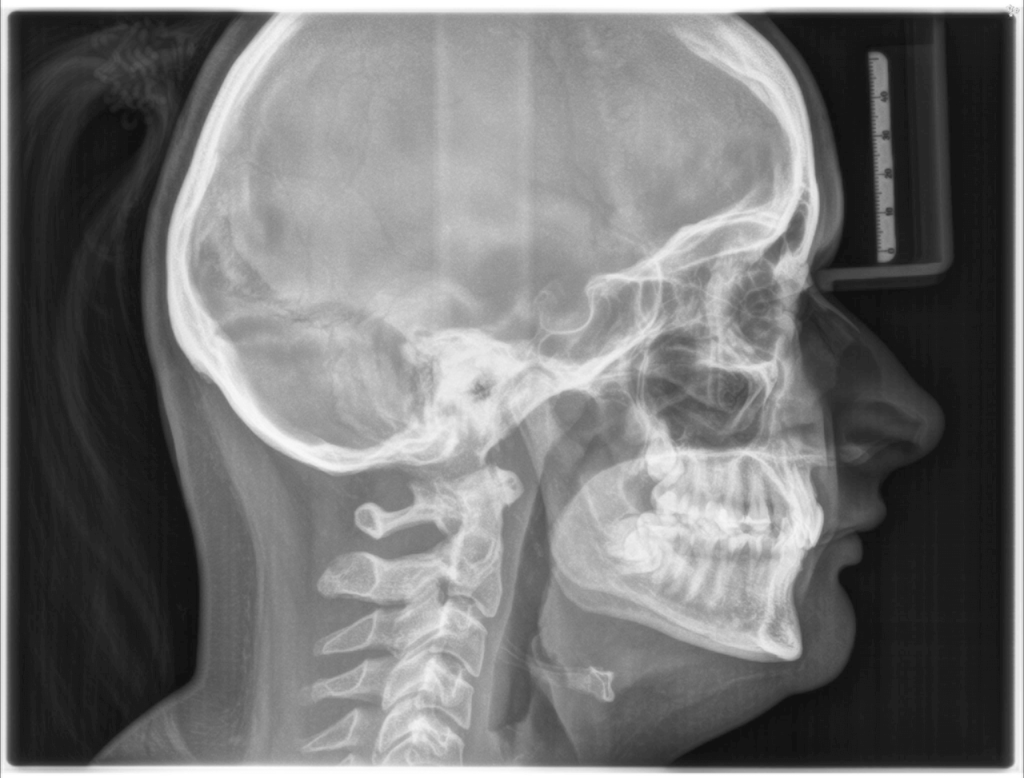

Dental physiotherapy is a modern approach to treating issues related to facial muscle tension, bite disorders, or temporomandibular joint (TMJ) problems. Although it may come as a surprise, many people suffer from headaches, tinnitus, or even back pain caused by improper jaw function.

Mr. Kacper Dettlaff uses modern rehabilitation methods that help restore proper function of the facial muscles and temporomandibular joints. In addition to manual therapy, patients receive individually tailored exercises and relaxation techniques that help reduce tension.